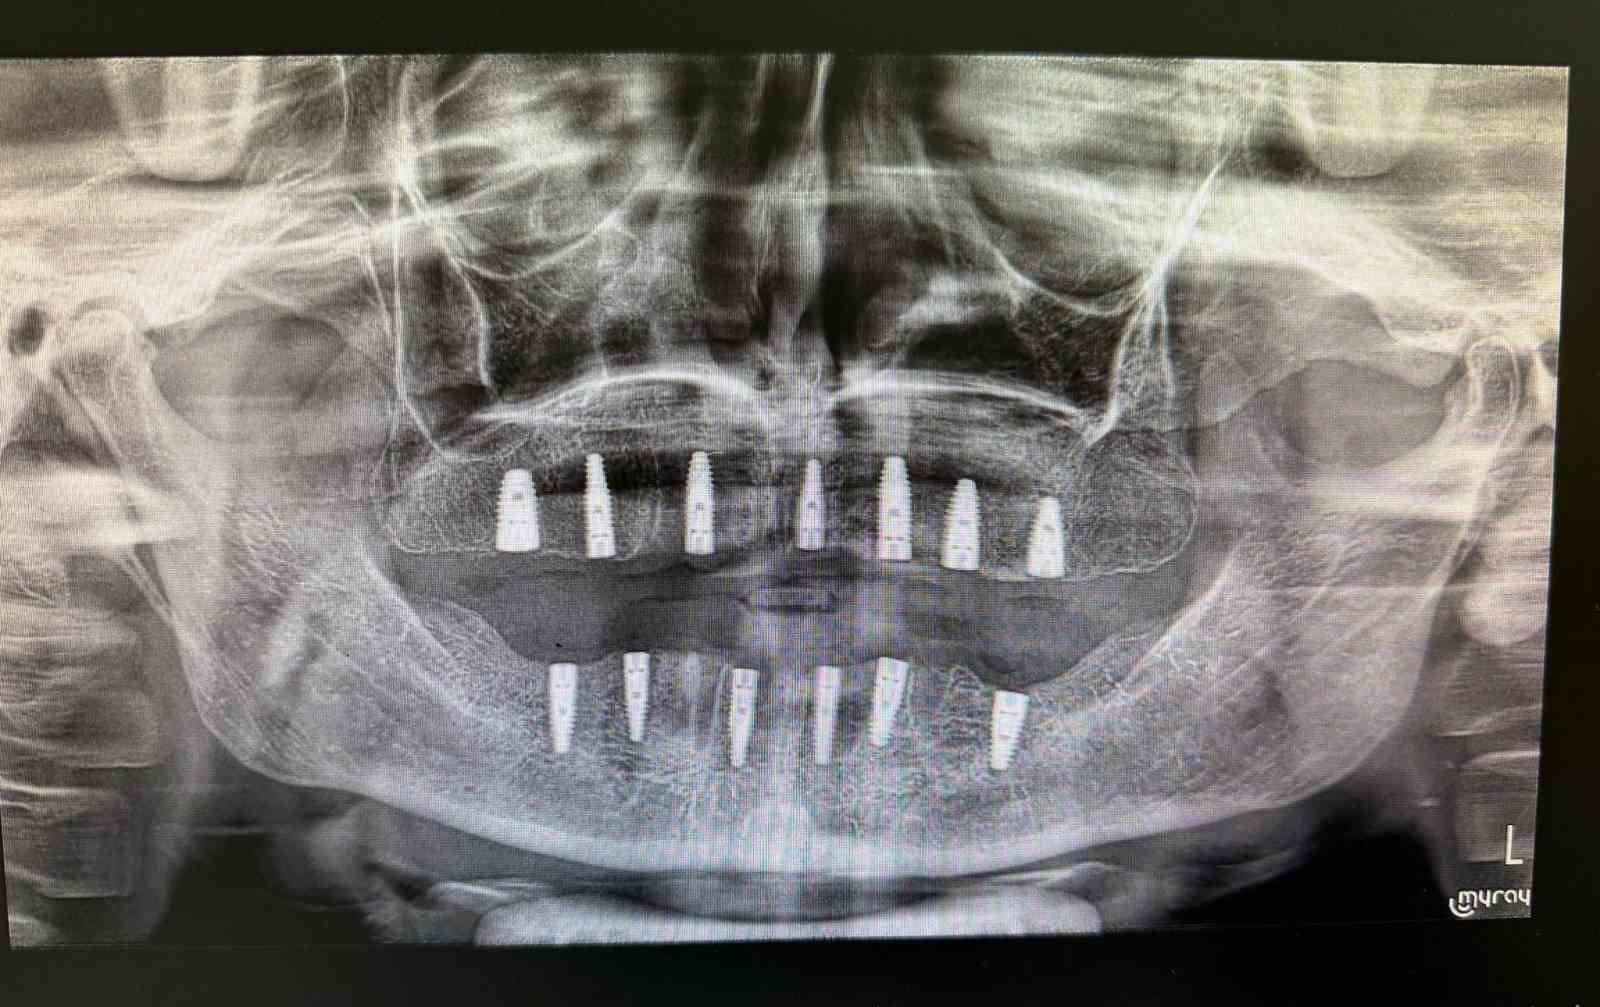

Merkezde görevli Uzm. Dt. Sefa Merve Arıkan tarafından gerçekleştirilen ameliyatta hastaya 13 adet implant yerleştirildi.

Diş implantı, çene kemiğine yerleştirilen ve eksik dişlerin işlevini üstlenen yapay diş kökleri olarak biliniyor. Genellikle dişini kaybetmiş veya hiç dişi bulunmayan hastalara uygulanan bu yöntem, hem estetik görünüm hem de çiğneme fonksiyonunun yeniden kazanılmasını sağlıyor.